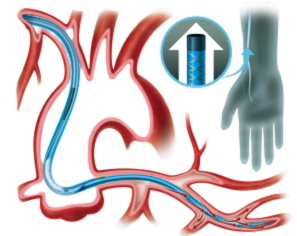

Flowguide

EXTEND THE REACH OF THE GUIDING CATHETER WITH REDUCED PRESSURE DAMPENING

The FlowGuide guide extension catheter reduces pressure dampening through 9 small perfusion openings in the distal shaft. A radiopaque soft tip for true distal end visibility facilitates precise device positioning. A stainless steel reinforcement embedded in the distal shaft ensures optimal lumen integrity and smooth device delivery. With a distal shaft length of 15 cm the FlowGuide is customized for optimal use in transradial procedures. The oval push rod guarantees no compromise with side along SDS delivery while securing optimal pushability.